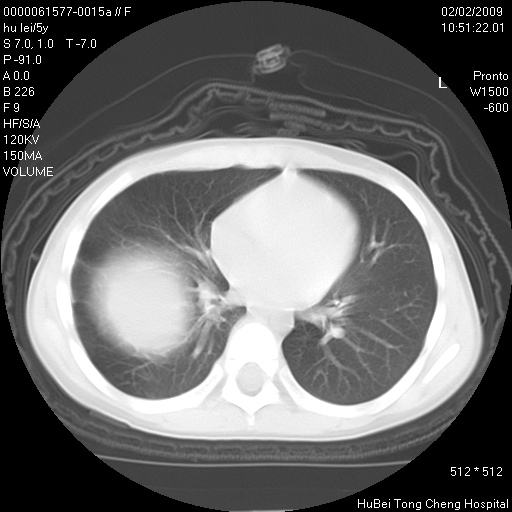

标题: PED1732:M5Y,右肺囊性占位!

患者:男,5。无明显不适,拍胸片考虑右肺囊肿。

行ct扫描,图象如下: